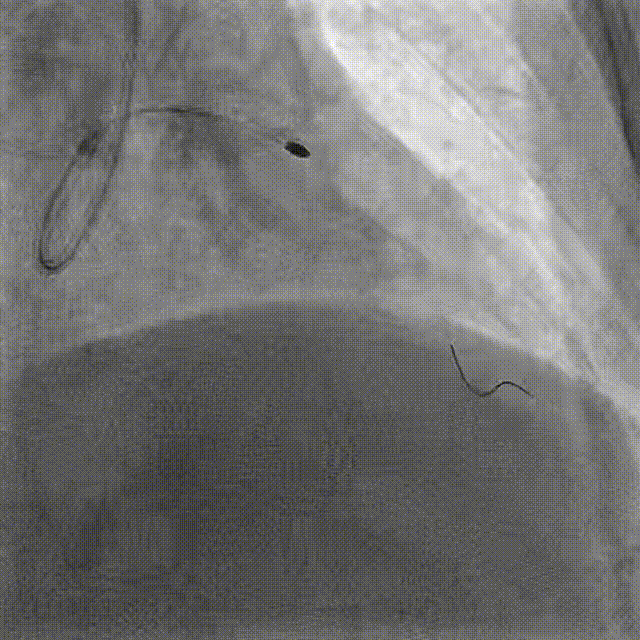

PCI-LAD TR, 7F EBU3.5

ROTA with 2.0mm burr

Angiography & Angioplasty NC 2.5*12mm

Stenting DES 2.5*24mm

Stent Optimization NC 2.5*12mm + NC 2.75*8mm

Lesion Preparation Cutting balloon 2.75*10mm @ 14atm

DCB Angioplasty DCB 2.75*25mm @ 8atm, 60s

Final Results